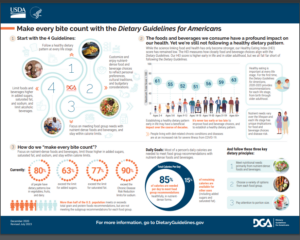

The food industry plays a significant role in the development of metabolic diseases. One key factor is the production and promotion of highly processed foods, often laden with excessive refined sugars, unhealthy fats, and additives. These processed foods, designed for convenience and taste, contribute to overconsumption of calories.

The Standard American Diet (SAD) significantly contributes to many health issues, such as insulin resistance and metabolic diseases. One of the key culprits is the high intake of refined carbohydrates, which rapidly elevates blood sugar levels and, over time, leads to insulin resistance.

High fructose corn syrup (HFCS), prevalent in the Standard American Diet (SAD), is associated with health issues, including insulin resistance and metabolic syndrome. HFCS’s high fructose content may lead to insulin resistance, increased visceral fat deposition, elevated triglyceride levels, and heightened inflammation.

Notably, HFCS is processed in the liver similarly to alcohol, contributing to non-alcoholic fatty liver disease (NAFLD), particularly in children. To support metabolic health and reduce the risk of metabolic syndrome, individuals should read food labels carefully, choose whole, unprocessed alternatives, and minimize their intake of HFCS-containing products.

In 2023, a staggering statistic looms over the United States – 1 in 5 children grapple with obesity. Reflect on the following list and consider how these foods dominate our children’s diets, contributing to the alarming reality.